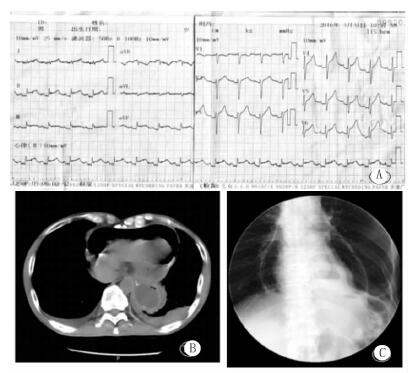

入院后复查心电图(2016年3月31日11:30)示:窦性心动过速,Ⅱ、Ⅲ、aVF 、V4-V6导联ST段抬高(图 1A)。肌酸激酶同工酶(CK-MB)和心肌肌钙蛋白(cTnI)在正常范围;血常规:白细胞总数19.9×109/L,中性粒细胞93.3%,血红蛋白124 g/L;C反应蛋白(CRP):165.5 mol/L;超声心动图(GE Vivid E9)检查示:肺气干扰,图像质量差。室壁运动无异常,少量心包积液。急诊胸部CT(图 1B)示:食管癌术后,心包积气,双侧胸腔积液,右上肺斑片影。上消化道碘油造影(图 1C)示:心包积气,食管癌术后,左侧胸腔胃,吻合口正常。入院诊断“心包积气,急性心包炎”,请胸外科、消化科等会诊后,给予CCU监护、吸氧、禁食,胃肠减压,全胃肠外营养,头孢哌酮舒巴坦静脉滴注等治疗,并抽取外周静脉血标本作血培养。4月1日患者诉说话、翻身或坐起时胸痛,平卧后胸痛可缓解。测体温正常,血压100/62 mmHg,复查CK-MB和cTnI均正常,降钙素原11.53 ng/mL。请感染科会诊后将抗生素改为亚胺培南西司他丁钠联合阿奇霉素抗感染治疗。4月3日复查全胸片(图 2)示:心包积气、积液(积气较2日前有所吸收),左侧少量胸腔积液。血常规:白细胞总数 9.7×109/L,中性粒细胞 80.1%,血红蛋白130 g/L;CRP 143.0 mol/L;降钙素原2.89 ng/mL。血电解质在正常范围。双侧血培养48 h(需氧和厌氧菌)均无细菌生长。继续禁食、胃肠减压、胃肠外营养、抗生素等治疗。

A:心电图示 Ⅱ、Ⅲ、aVF、V4-V6导联 ST段抬高; B:胸部CT检查示,食管癌术后,心包积气,双侧胸腔积液,右上肺斑片影;C:上消化道碘油造影示,心包积气,食管癌术后,吻合口正常 图 1 患者入院心电图(A)、急诊胸部CT(B)和上消化道碘油造影(C)结果